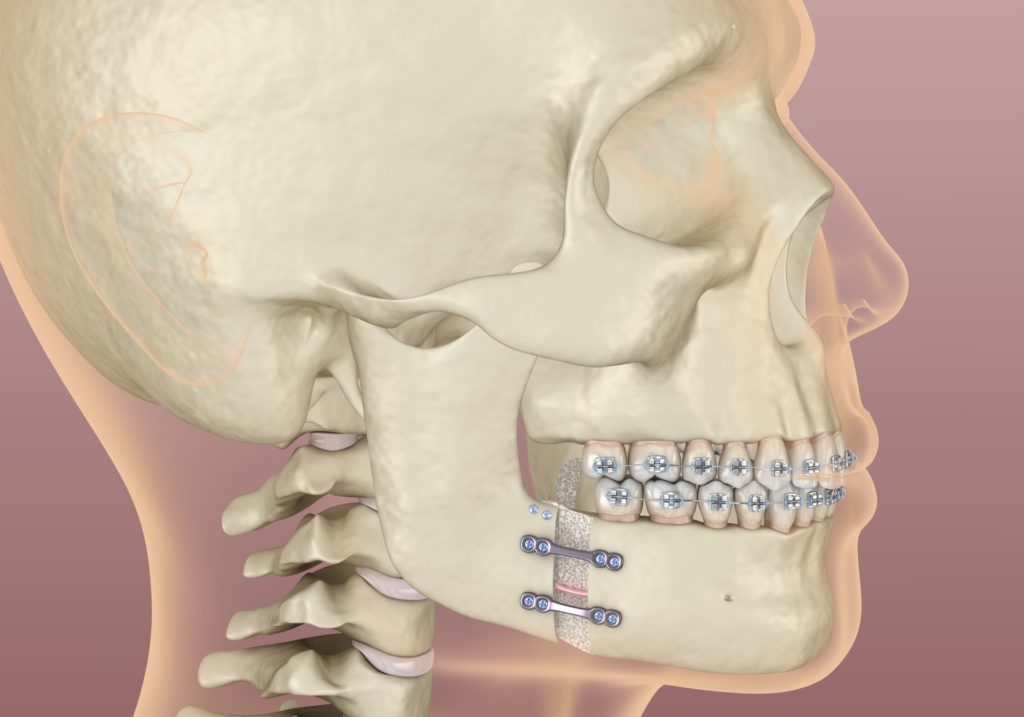

Orthognathic surgery is an exclusive branch of oral and maxillofacial surgery and is part of orthodontic treatment. It involves the alteration of the jaws to modify their adjustment and position to improve the functioning of the mouth. Orthognathic surgery is used to correct a severe malocclusion resulting from a misaligned jaw. It is usually completed in conjunction with orthodontic treatment or braces. The procedure is performed under anaesthesia. Surgery will require three to several days of hospitalisation.

To obtain the best fit of the upper and lower teeth in the new position of the jaws, most people require some orthodontic treatment after the surgery to improve the tooth alignment. This will take three to twelve months, after which the braces are removed (and the new braces may replace them). Everyone’s jaw problems differ, so consult a specialist and explain your expectations. Your medical providers will explain their recommendations to solve your specific issues and what you can expect.